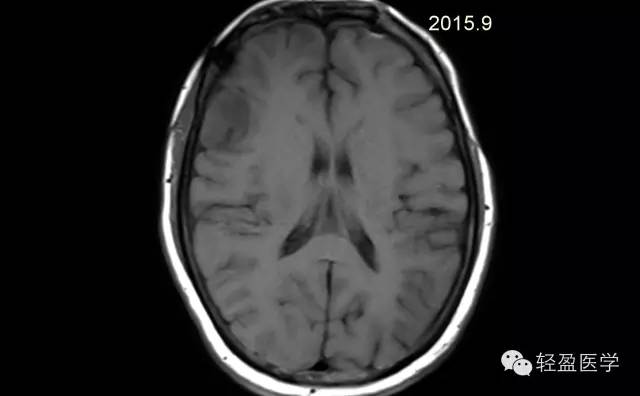

病理为:小细胞恶性肿瘤,考虑为(外周)原始神经外胚层肿瘤,(复发)。以下是病例结果及分析。